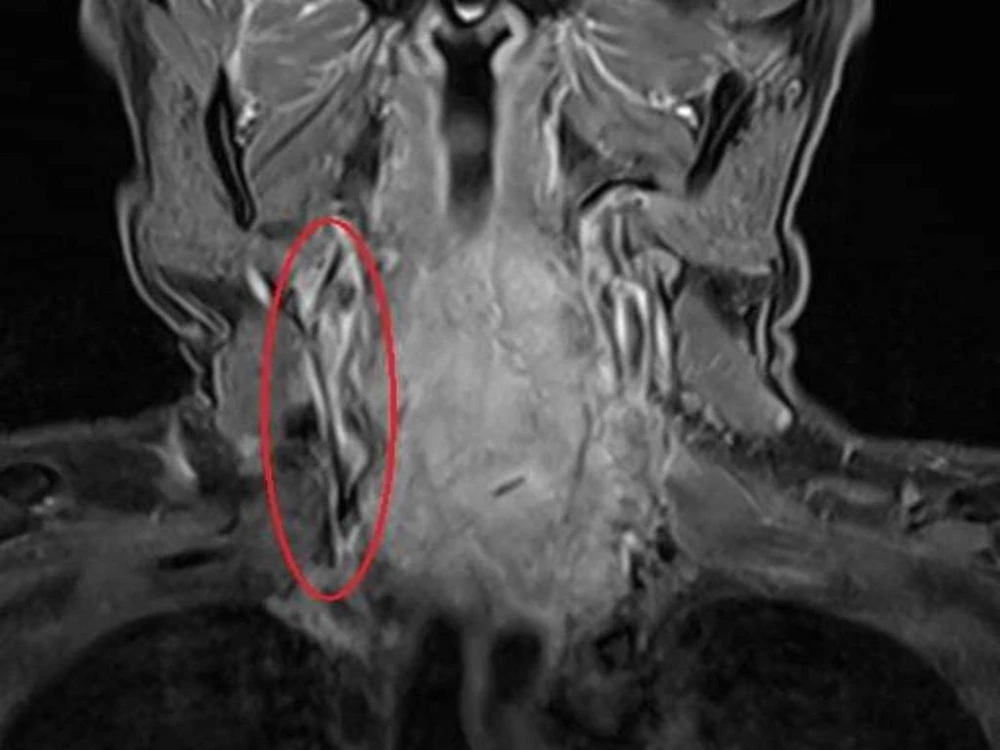

Hình ảnh chụp MRI cho thấy người bệnh bị áp xe đốt sống cổ. Ảnh: BVCC

Qua kiểm tra, các bác sĩ phát hiện vùng sau cổ anh H. có khối áp xe lớn, xét nghiệm cho thấy bị nhiễm khuẩn máu nặng. Người nhà cho biết anh H. bị thoái hóa đốt sống cổ hai năm nay, điều trị nhiều nơi nhưng không khỏi. Trước khi nhập viện một tuần, vùng cổ anh H. đột ngột đau nhức nhiều hơn, gia đình nghĩ bị trúng gió nên đưa anh đi cắt lể nặn máu độc ra ngoài.

Sau khi cắt lể, tình trạng của anh trở nên nặng hơn, cổ ngày càng sưng to, đau nhức không thể cử động.